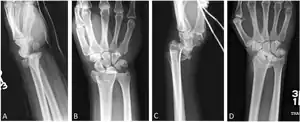

A Barton fracture is a type of wrist injury where there is a break of the front or back of the radius nearest the hand, resulting in the wrist being pushed out of place.[1] It typically occurs after falling on on top of a bent wrist.[2]

There exist two types of Barton's fracture – dorsal[3] and palmar, the latter being more common. The Barton's fracture is caused by a fall on an extended and pronated wrist increasing carpal compression force on the dorsal rim. Intra-articular component distinguishes this fracture from a Smith's or a Colles' fracture.

Treatment of this fracture is usually done by open reduction and internal fixation with a plate and screws, but occasionally the fracture can be treated conservatively.

Additional images